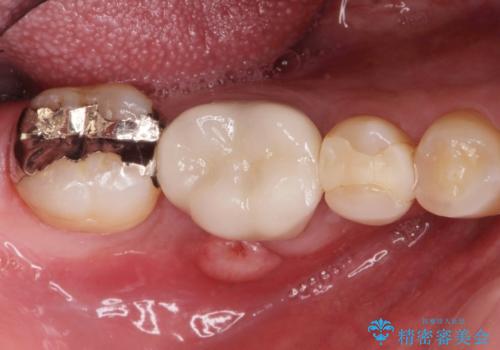

汚れの溜まりやすい銀歯を精度の高いセラミック治療で改善